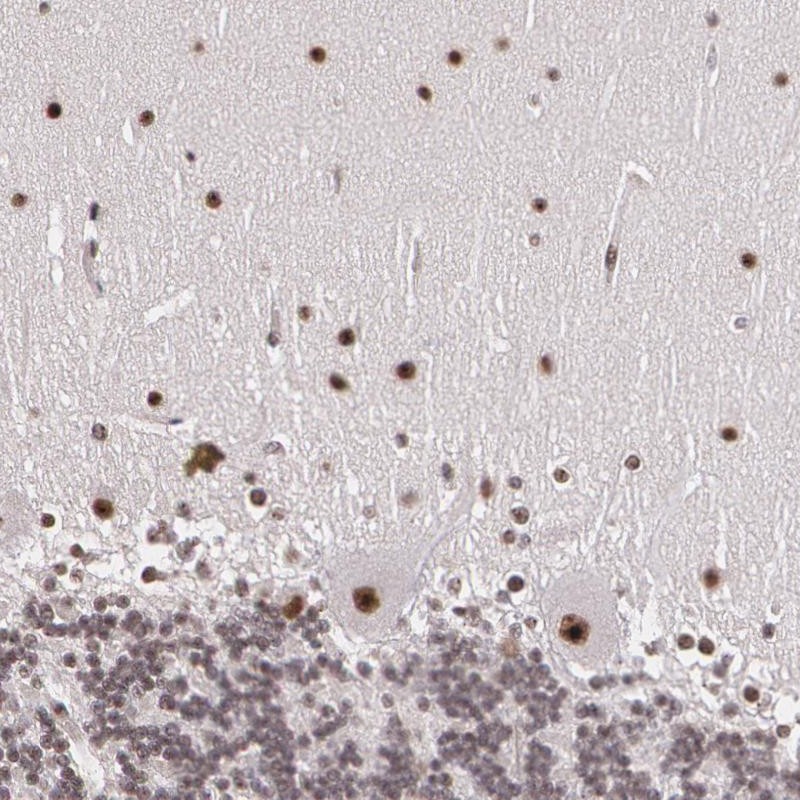

Immunohistochemical staining of human cerebellum shows strong nuclear positivity in purkinje cells and cells of molecular layer.